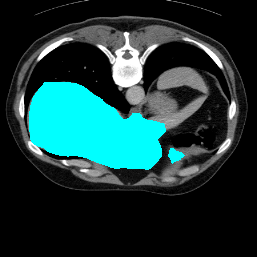

Support

Label

Proposed

In order to assess the performance of the proposed method, we compare the performance of the proposed model with excellent models in recent years. Table 1 and Table 2 shows the comparison results of different models in setting1, while Table 3 and Table 4 shows the comparison results of different models in setting2 on the data set in recent years. PANet[25] is the most widely influential few-shot model in the field of few-shot image segmentation on natural images. SENet [18] is the first few-shot segmentation model proposed for medical images. SSL-ALPNet[19] introduced the milestone of using superpixel self-supervision to train few-shot medical image models. RPNet[29] is a supervised method with a recursive mask optimization module to iteratively optimize the segmentation mask, [27] adapt it into the same self-supervision learning framework and applies setting1 to it and denoted as SSL-RPNet; CRAPNet[27] is the latest SOTA model for 2023. Compared with CRAPNet, our method outperforms most of the state-of-the-art models and only slightly outperforms CRAPNet. Figures 3 and 4 show examples of the model’s segmentation predictions on different datasets, respectively; The first row is the support map, the second row is the label map, and the third row is the segmentation prediction of the model.